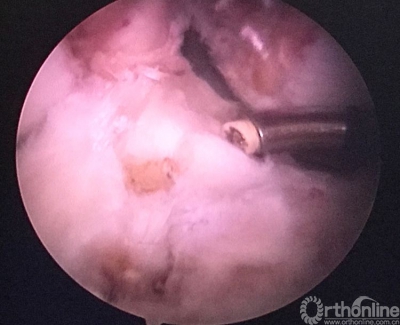

关节镜检查见重建的韧带已经消失。

原来重建的ACL胫骨隧道内口偏前(等离子刀头所指处)。

现等离子刀头所指处为外侧半月板前角游离缘。左下方2个等离子刀烧灼处为原内口及准备返修的内口。